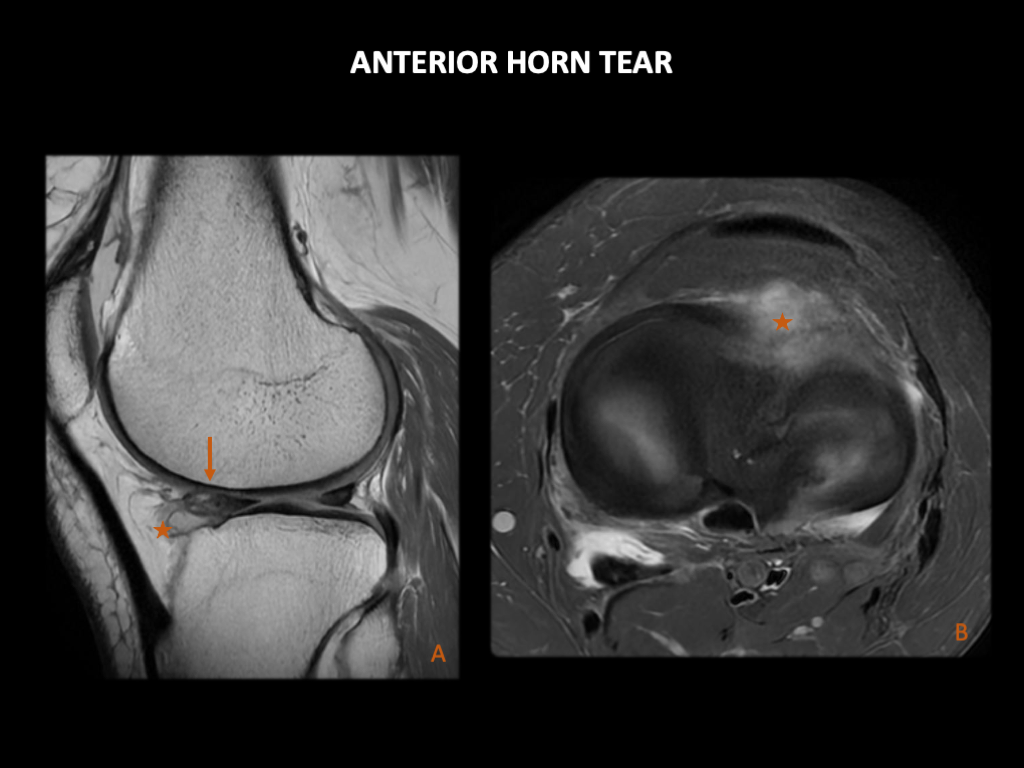

5、前角撕裂传统上认为,半月板的前角对膝关节稳定性几乎没有影响。然而,近年来的研究证明它们可能比之前认为的扮演着更重要的角色。前角撕裂很少见,并且难以通过关节镜诊断,但它们通常与半月板旁囊肿有关,因此MRI在其诊断中发挥着重要作用。

图 25:一名65岁女性的半月板前角撕裂。左膝3T MRI:(A)矢状位PD和(B)轴位PD FS显示外侧半月板前角有线性高信号,与该位置的撕裂一致(箭)。旁边有一个半月板旁囊肿(星号)。